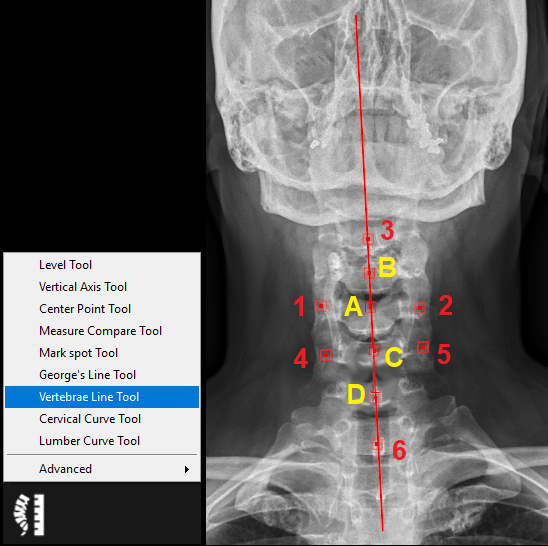

9.5.7. Vertebrae Line Tool

The vertebrae line tool is used to draw a line to represent the spinal canal based on six points. Follow the instructions below to use this tool:

1.      Select the ‘Vertebrae Line Tool’ from the chiropractic toolbox and plot the following points (in red):

2.      Point 1: click on the left/right side of the vertebral body.

3.      Point 2: click on the opposite side (i.e. right/left) of the vertebral body.

4.      A center point A will automatically appear between point 1 and 2.

5.      Point 3: click on the spinous process.

6.      A center point B will appear between point A and point 3.

7.      Point 4: click on the left/right side of the following vertebral body.

8.      Point 5: click on the opposite side of the following vertebral body.

9.      A center point C will appear between point 4 and 5.

10.    Point 6: click on the spinous process.

11.     A center point D will appear between point C and point 6.

12.     A line will appear which passes through points A-D and it represents the spinal canal.

13.     You can adjust the point positions by clicking on the point and dragging it to a new position.